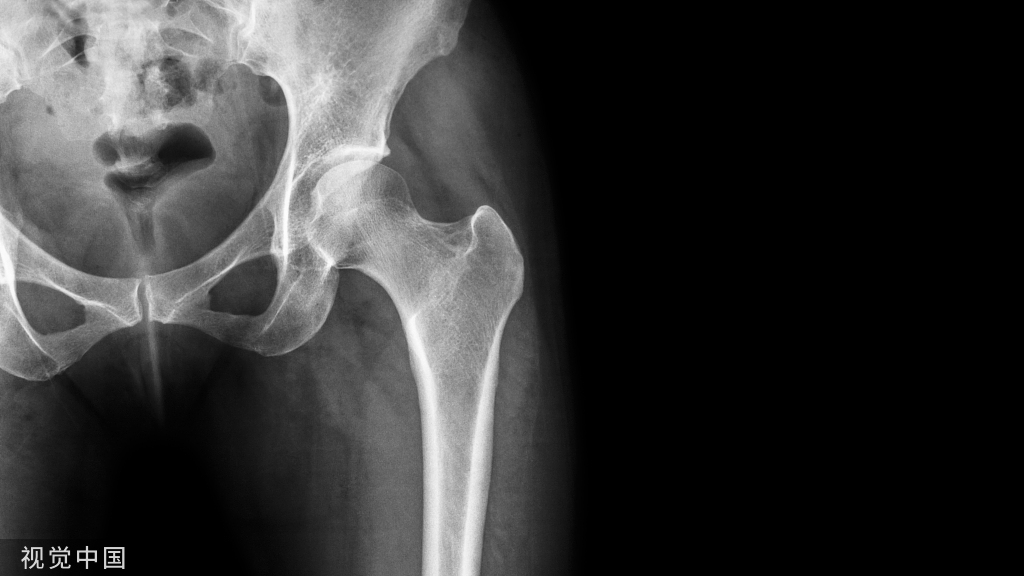

髋关节置换术后的康复

定义:是指应用人工材料制作的全髋关节结构植入人体以替代病损的自体关节,从而获得髋关节功能。是人体矫形外科中较大的重建手术。

适应证:主要适用于以下疾患导致髋关节功能严重丧失、伴有严重疼痛且通过严格保守治疗不能缓解的患者:①骨性关节炎;②类风湿性关节炎;③髋部严重骨折;④股骨头缺血坏死;⑤髋关节畸形

案例分析患者,男,65岁,髋关节疼痛,负重时加重。患者两年前发现左侧臀部及左大腿前部隐约疼痛,1年前屈髋活动受限,现髋关节疼痛,负重时尤甚,不能深蹲,呈避痛步态。MRI提示股骨头缺血性坏死。现入院行全髋置换术。

8.X线检查  含双侧髋关节的骨盆正位片和患侧髋蛙式位片。与健侧进行对比,了解手术关节有无畸形、增生 、对线等影像学的改变,作为重要的手术参考依据。